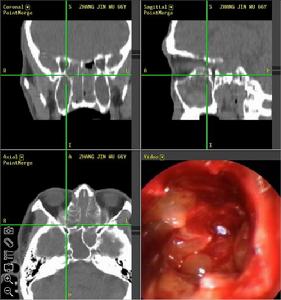

咽喉息肉CT圖病因